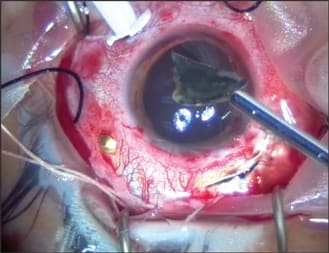

A 20-year-old male sustained an intraocular foreign body (IOFB) in his left eye by hitting a hammer against a large metallic object. He presented to the emergency room 1 day after the injury. On examination, his visual acuity was 20/200, and a large nasal conjunctival hemorrhage was observed with hypotony and clear cornea and lens. On indirect funduscopy, a metallic intraocular foreign body was observed stuck in the inferior retina at the equator with a local retinal detachment, whitening of the retina around its edges, and a mild vitreous hemorrhage. The intraocular foreign body was demonstrated on orbital CT (Figure 1). An exploration revealed a 4 mm entry wound, extending posteriorly from the limbus at the nasal side. The wound was sutured with Vicryl 7/0 suture, an encircling #41 solid silicone band was placed (Figure 2), and a pars plana vitrectomy was performed during the primary procedure. The intraocular foreign body was released from its adhesions to the retina (Figure 3) and removed with a magnet (Figure 4) through a previously prepared sclerotomy, revealing a large retinal tear (Figure 5). The intraocular foreign body outside the eye is shown in Figure 6.

Figure 3. Intraoperative view of the IOFB, local retinal detachment, and retinal whitening.